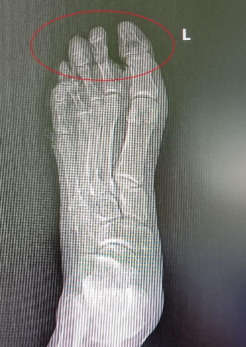

近大半年,陈大叔病情加重,左脚出现反复红肿和伤口渗液,疼痛难忍。他在当地医院治疗后伤口一直不能愈合,逐渐出现大部分足趾坏死、足部溃烂发黑的情况,足部体温因缺血无法测出,甚至连骨头都清晰可见。

术前前足组织坏死,骨外露